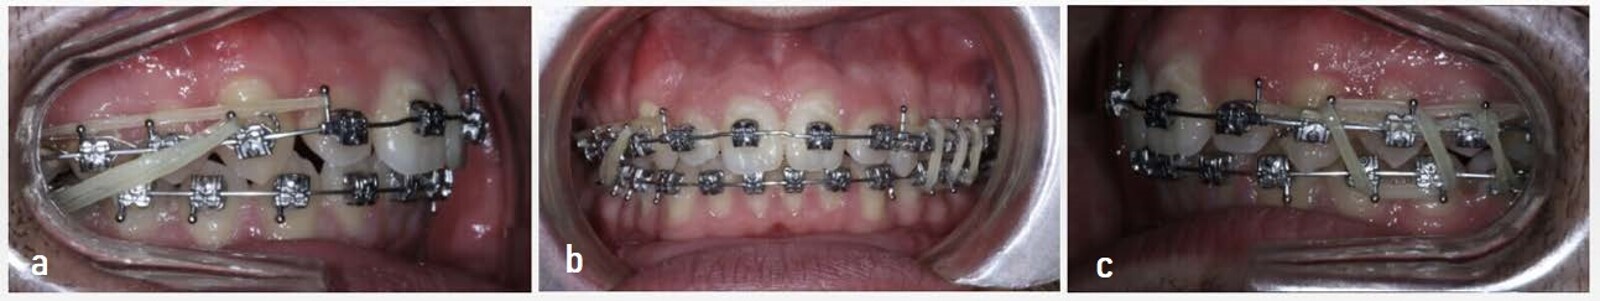

After performing all relevant studies and tests, a Class II CMA was used for the molar de-rotation and the canine distalisation, and buttons were cemented on teeth #36 and 46 for the elastics. An Essix-type transparent retainer was used in the mandibular arch to facilitate the distalisation of the maxillary arch. The protocol for the elastics was 6 oz during the first month and then 8 oz until Class I canine overcorrection had been achieved (Fig. 9).

After a few months, owing to the canine extrusion caused by the elastics, we had to change the position of the distaliser to the maxillary left premolar and consequently placed the button on tooth #37 to increase the distance of the elastic. For the maxillary right quadrant, the canine situation did not require any changes. At this stage of treatment, 8 oz elastics were used (Fig. 10). This device was used for a total of seven months, in which time a Class I molar overcorrection was intentionally obtained (Fig. 11) in case of possible relapse. The study models were taken after removal of this appliance (Fig. 12).

After removing the Class II CMA, we used the Carriere SLX Bracket System (Henry Schein Orthodontics) in both arches with a 0.014 in. copper nickel–titanium (NiTi) archwire. The maxillary arch was undertied from the molar to the canine in both quadrants in order to retain the previously obtained results. In turn, we started using Class II short 2.5 oz, 3/16 in. elastics for night-time use until a Class I occlusion had been established (Fig. 13). The archwire sequence was 0.014 × 0.025 in. and 0.017 × 0.025 in. copper NiTi, finishing with 0.019 × 0.025 in. CNA.

The use of Class II elastics and posterior box elastics helped to achieve the correct occlusion in both arches. Crimpable hooks were placed distal to each maxillary lateral incisor in the strongest archwire (0.019 × 0.025 in. CNA). This facilitated the distalisation of the anterior sector through a power chain placed in the tooth #15–14 hook and tooth #25–24 hook positions. This did not touch the canine so that the traction caused by the elastic would not disrupt the Class I canine relationship that had been achieved (Fig. 14). In the final stages, owing to the inability to fit tooth #25 correctly, the distal archwire of the first premolar was cut to facilitate the action of the elastics and achieve some contact between the tooth and its antagonist (Fig. 15).